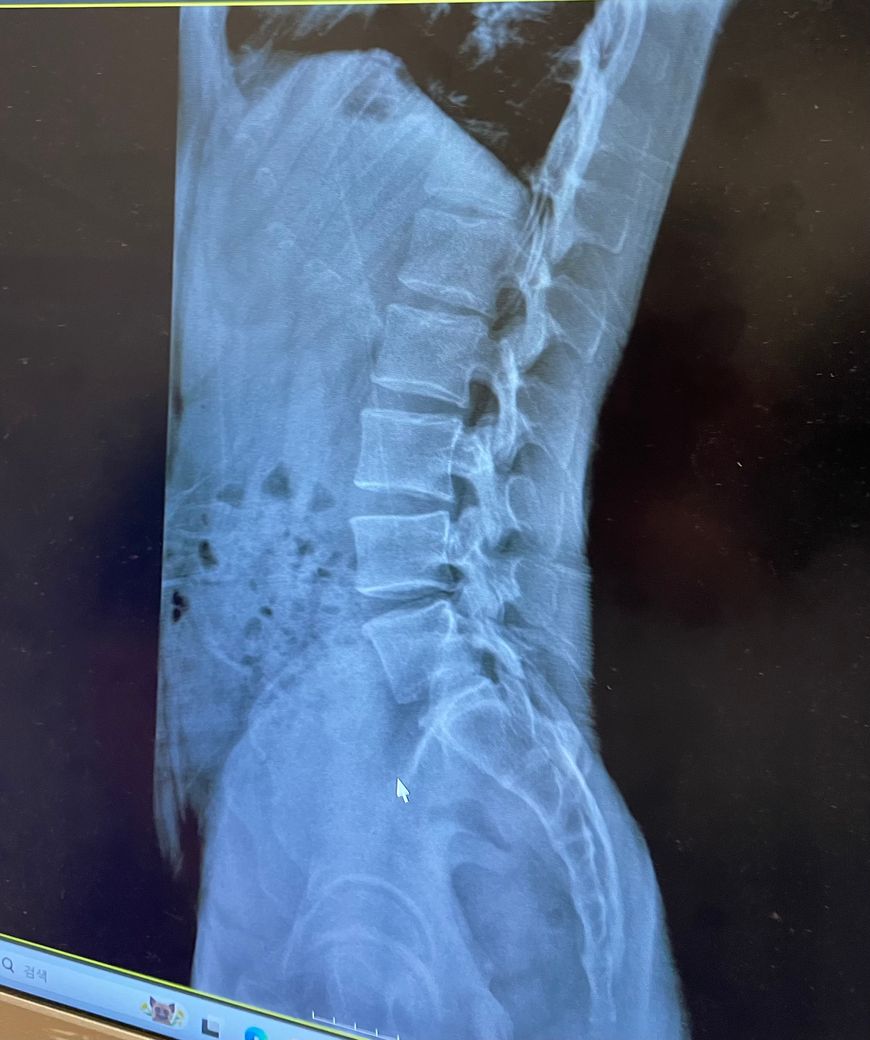

Q2. 사진 상으로는 저 정도면 어느정도 수준이라고 볼 수 있을까요? 회복이 가능한지, 앞으로 평생 관리해줘야 되는지 궁금합니다.